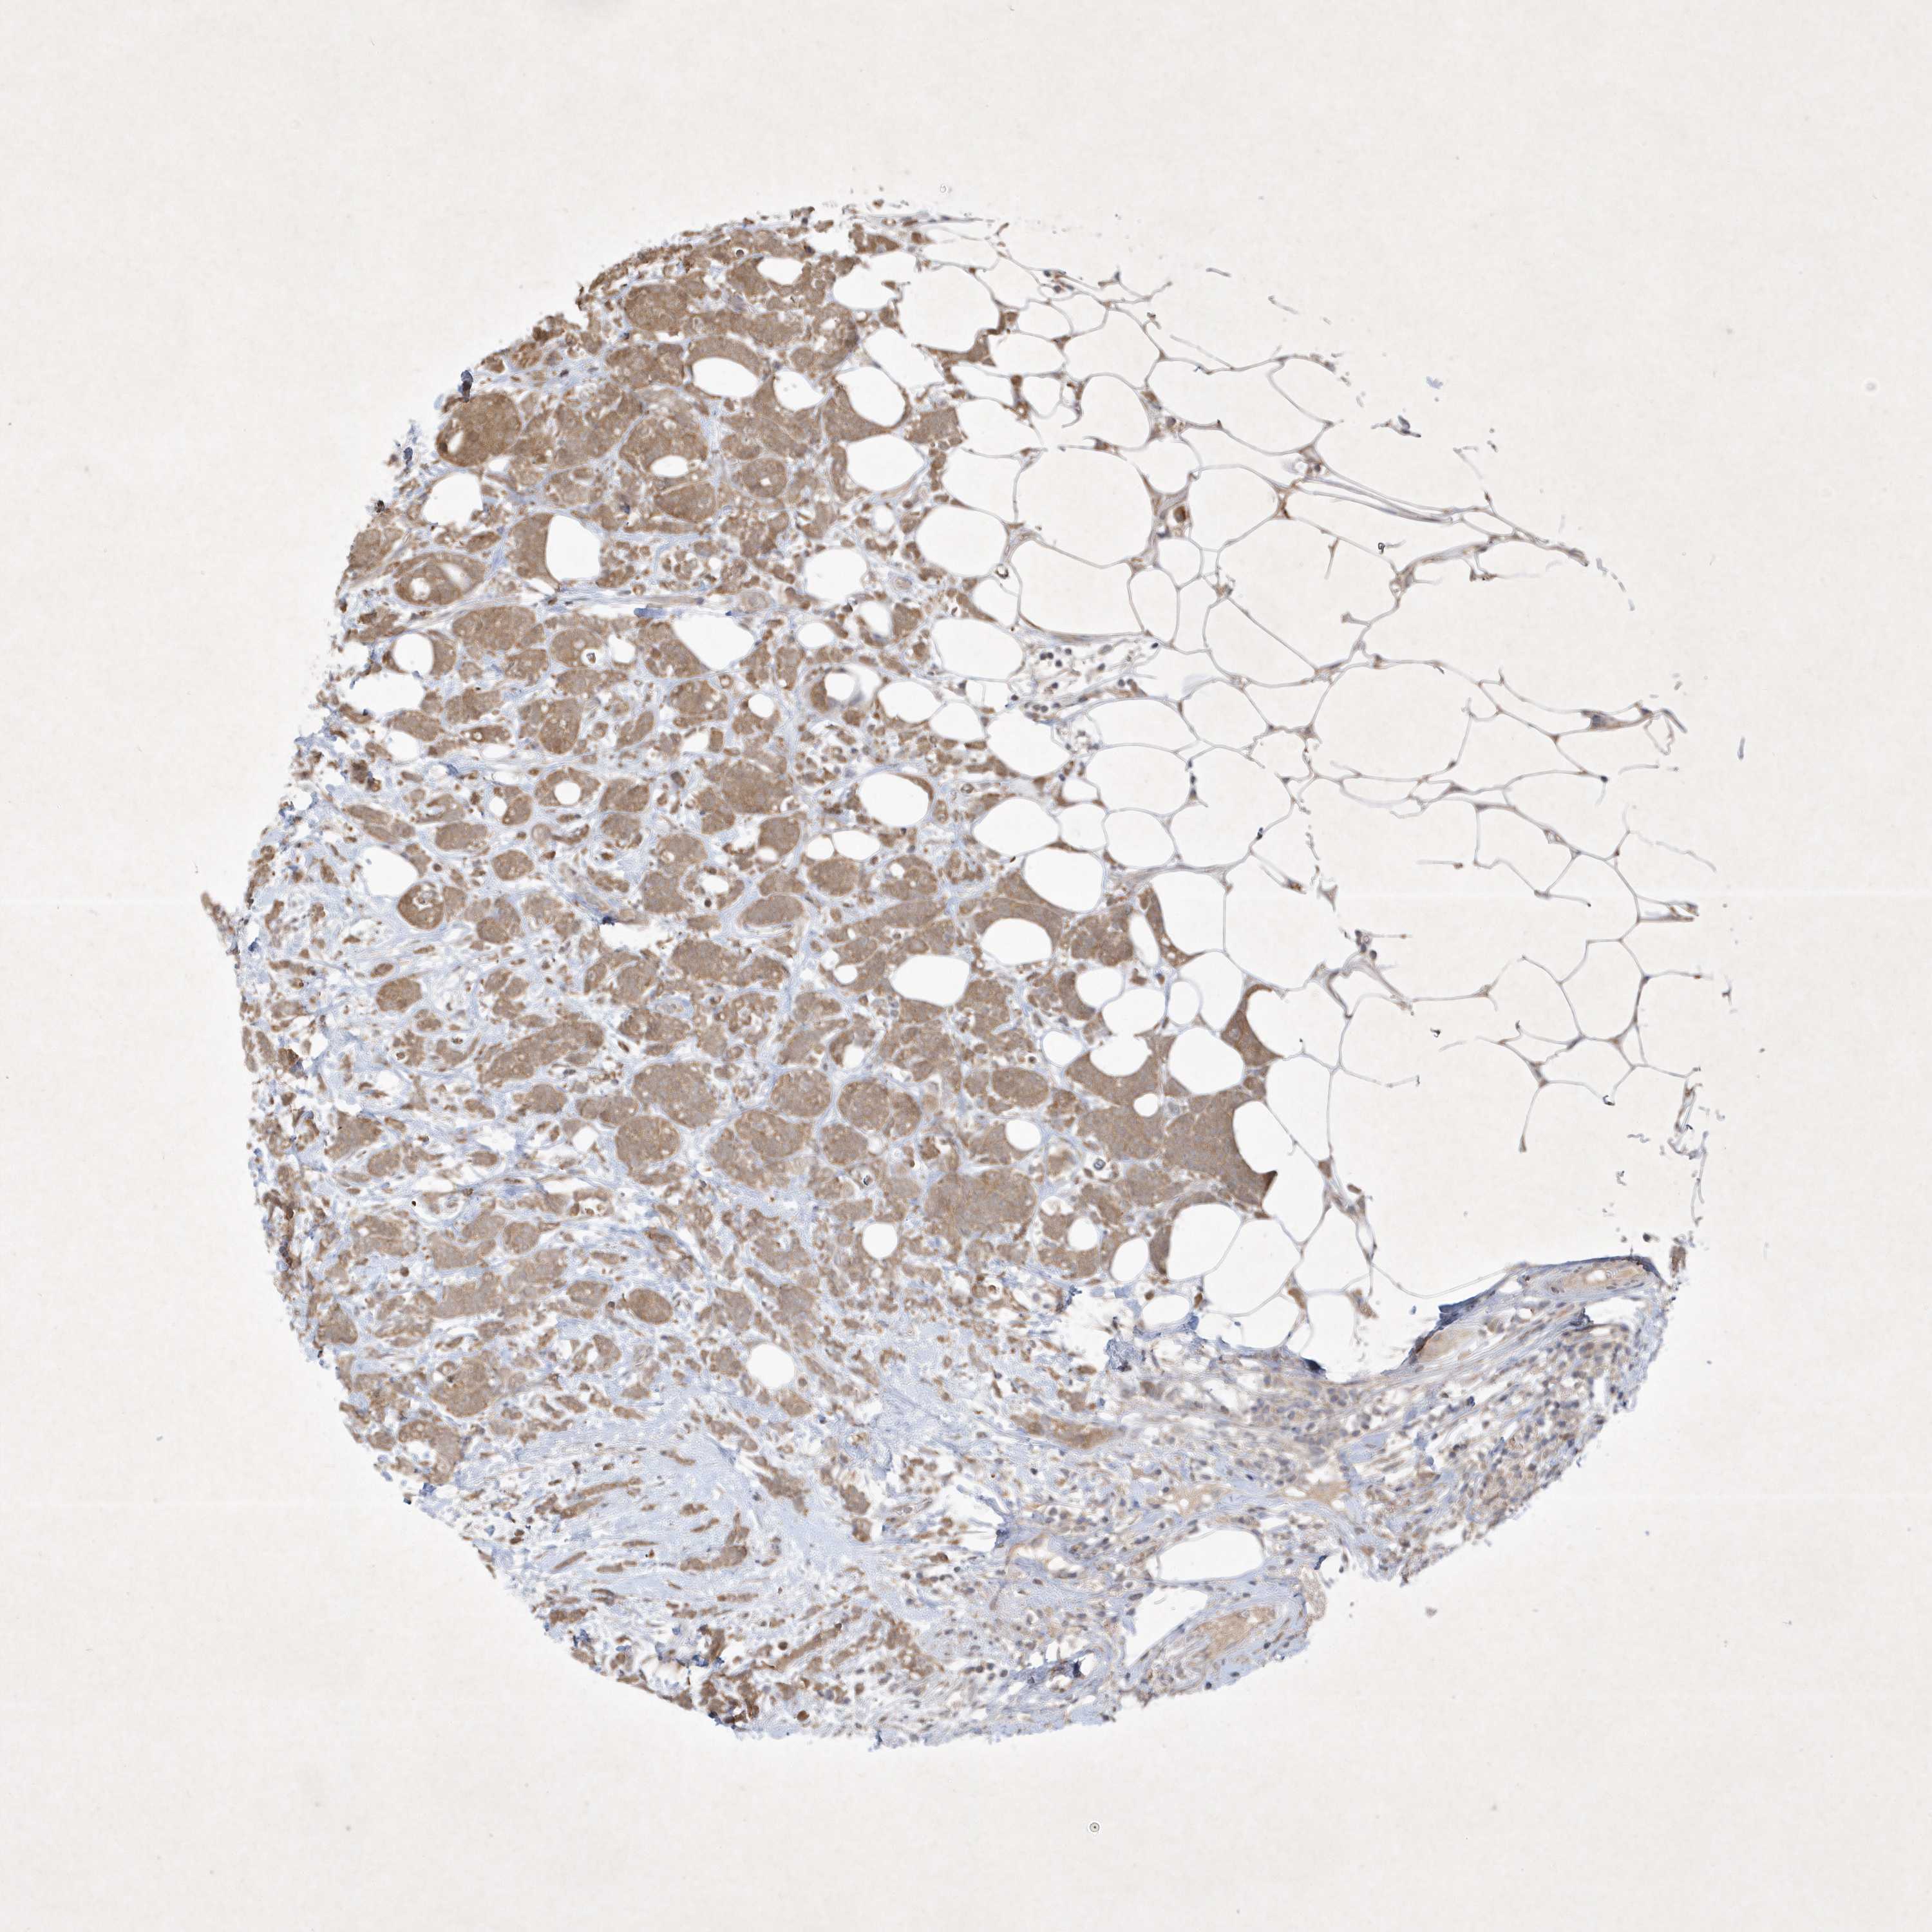

BRCA TCGA BRCA VALIDATION PROTEIN EXPRESSION